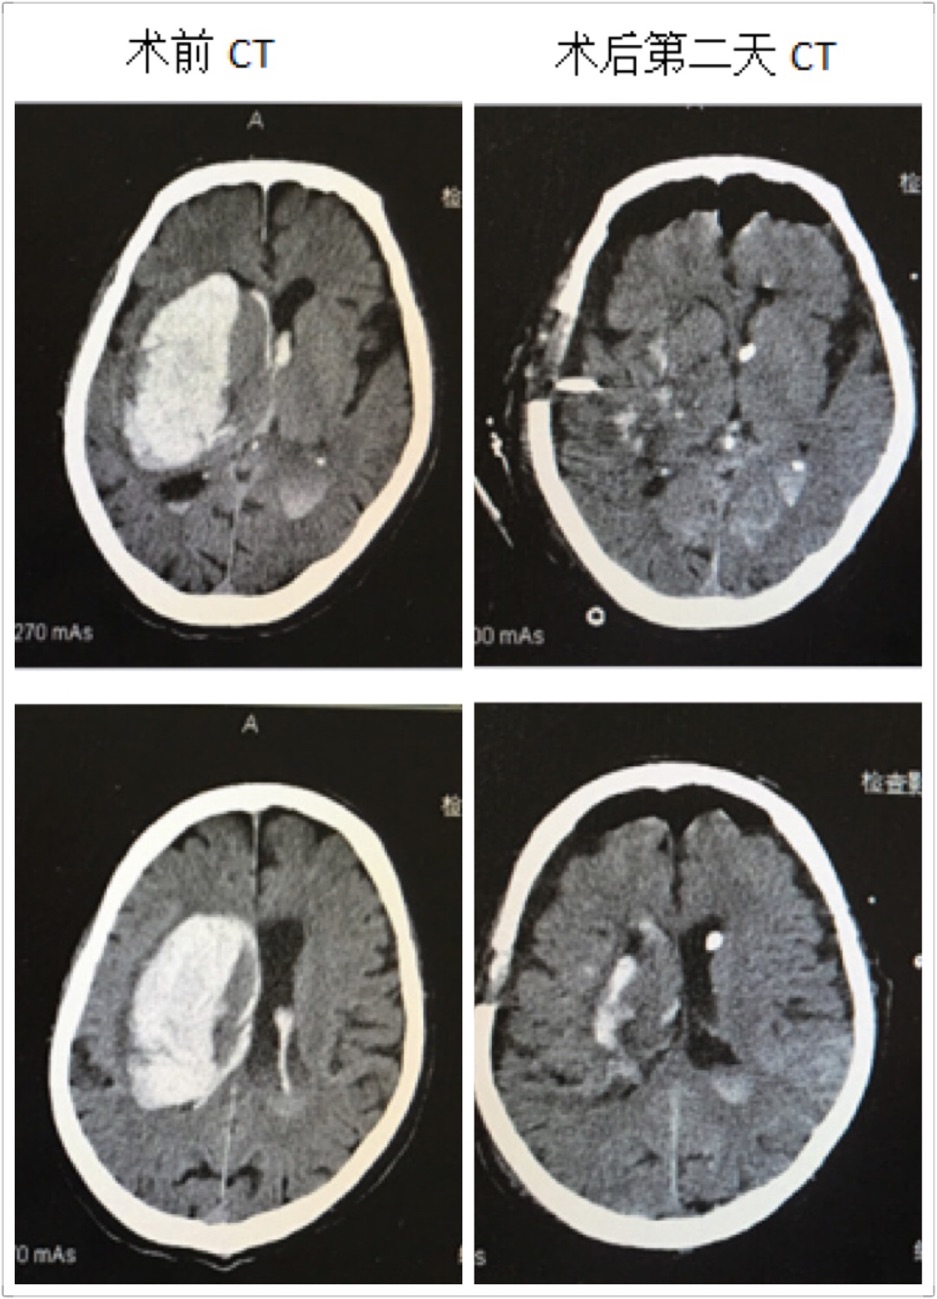

近日,探花av 神经外科成功救治一名高龄脑出血患者,并顺利康复出院,取得了满意的疗效。这位男性患者86岁,出血量约120ml,入院后处于深昏迷状态,Glasgow评分仅3分,一侧瞳孔散大,颅内高压频繁喷射性呕吐,病情危重,随时有死亡的可能。在这例高龄脑出血患者入院后,探花av 神经外科王钢副主任医师放弃休息时间,立即组织医疗小组,商讨治疗方案,像这样大量脑出血手术必须手术治疗。在保证血肿清除率及创伤小、出血少的前提下,在我科完成多例神经内镜下血肿清除术的基础下,王钢副主任医师提出:这位高龄患者可以采取小骨窗和神经内镜下清除血肿。

在王钢副主任医师的带领下,和麻醉科曹淑梅主任,杨克副主任一起,经过详细的术前讨论,制定周密的手术方案,急诊在全身麻醉下行脑出血小骨窗及神经内镜下清除血肿。手术十分顺利,手术历时2小时,骨窗大小直径约3cm,术中完全清除血肿,出血极少,术中未输血。术后第2天患者意识状态明显好转,由昏迷转为呼唤睁眼,出院时患者意识已经清醒,并且能够正常交流。